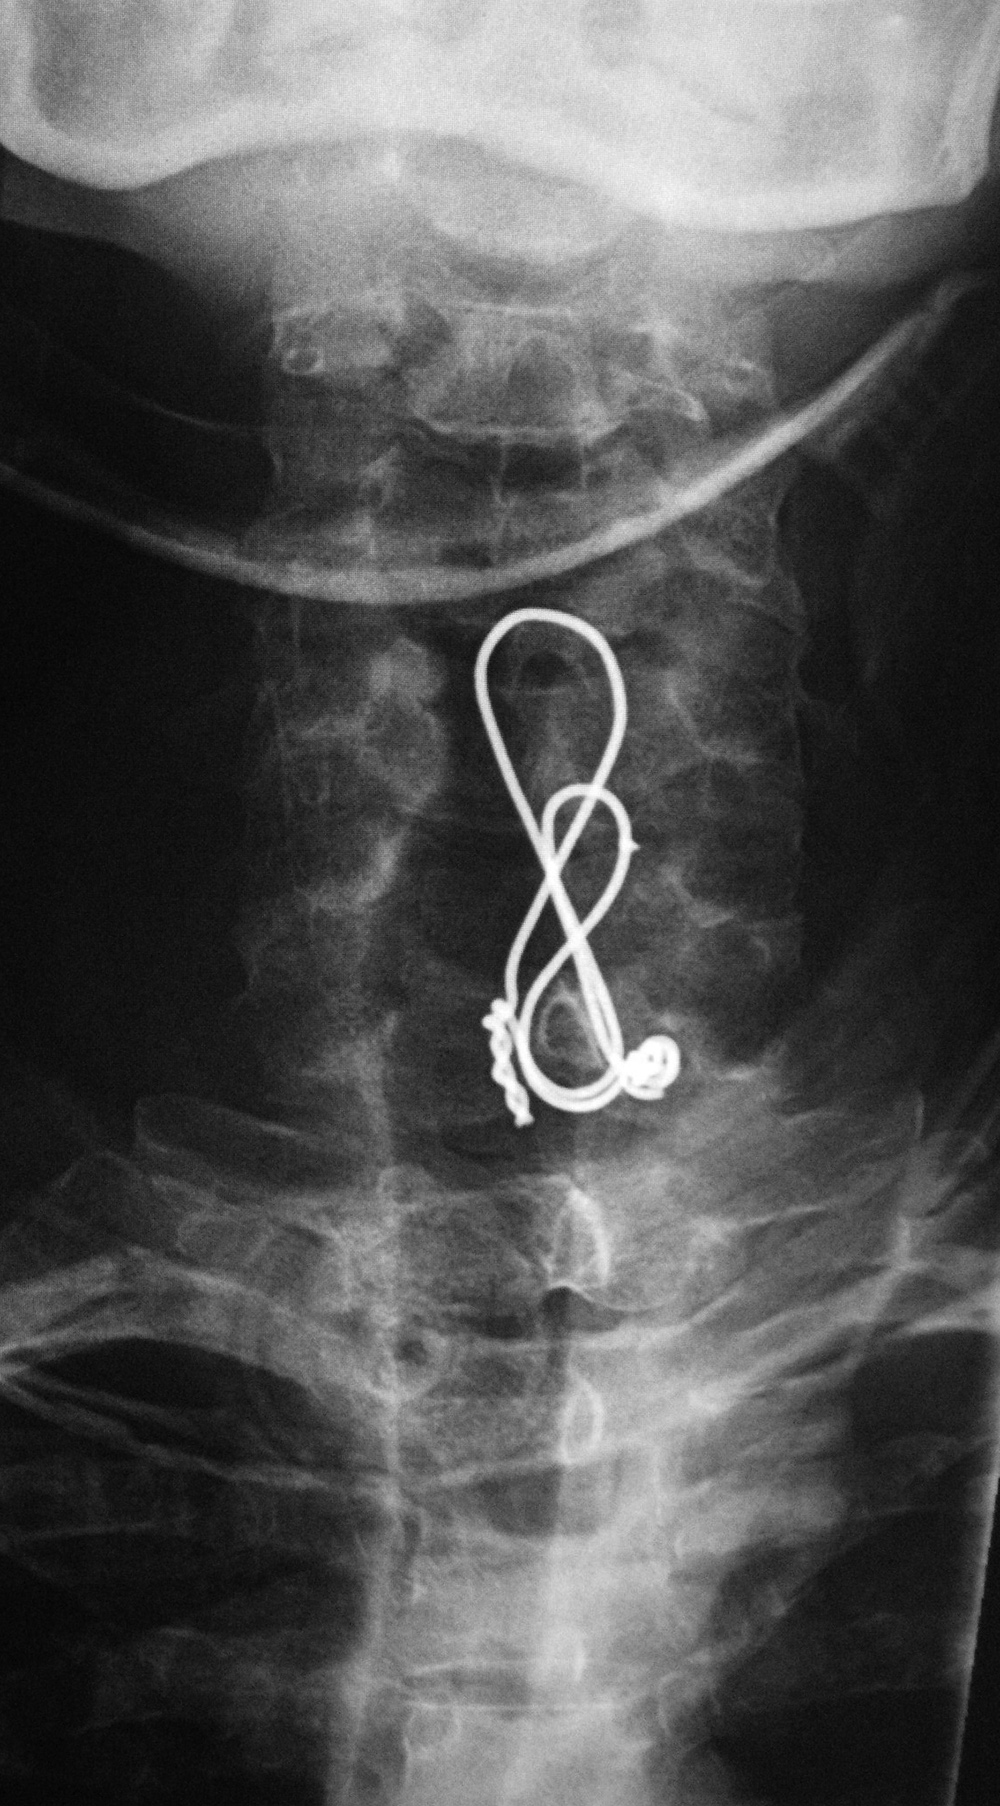

Posterior cervical wire figure of 8 construction - AP view |

Posterior cervical wire figure of 8 construction - lateral view |

Posterior cervical wire figure of 8 construction - sagittal CT reformatted image |

44 year-old man with C7 vertebral fracture. Posterior figure of 8 wire fixation extends from C4 to C7 |